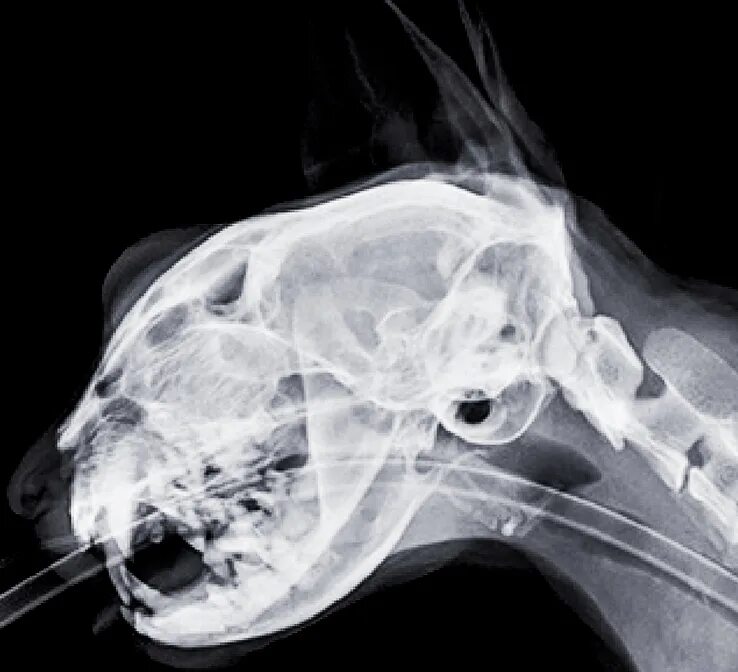

Source x rays